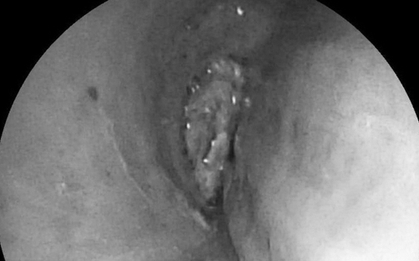

Một trường hợp y khoa gây sốc vừa được ghi nhận tại Tanzania: một người đàn ông 44 tuổi đến bệnh viện vì vùng ngực dưới núm vú phải chảy dịch mủ kéo dài 10 ngày. Bệnh nhân không hề sốt, không khó thở, cũng không có biểu hiện đau đớn nào bất thường.